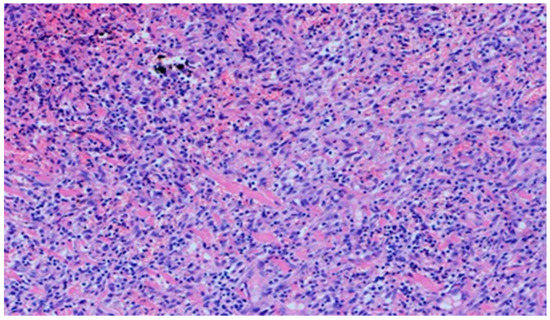

On day 5 of the experiment, slight differences in the wound healing process were observed. Inflammation was present in all wounds and the surrounding tissues, however, with a different intensity, type and depth of infiltration. In group D1, treated with the 1% propolis ointment, there was a moderately dense granulocytic infiltration reaching the dermis. Wounds in group D2, treated with the 1% nanosilver ointment, were characterized by a granulocytic infiltration with a low density and depth of infiltration reaching the dermis. In wounds treated with a mixture of 1% propolis and 1% nanosilver, there was a large granulocytic inflammatory infiltration reaching the depth of the adipose tissue. Wounds treated with sulfathiazole were characterized by a small, mixed infiltration reaching the dermis. On day 5 of the treatment, all wounds from the experimental and control groups did not show any epidermization features. Superficial necrosis was low in the experimental groups and a high degree of necrosis was observed in the sulfathiazole-treated control group. The histopathological findings from day 5 are presented in Table 8 and Figure 13 and Figure 14.

Figure 14. Necrosis, with granulocytic inflammatory infiltration (100×, H-E), in the wound treated with sulfathiazole, on day 5.